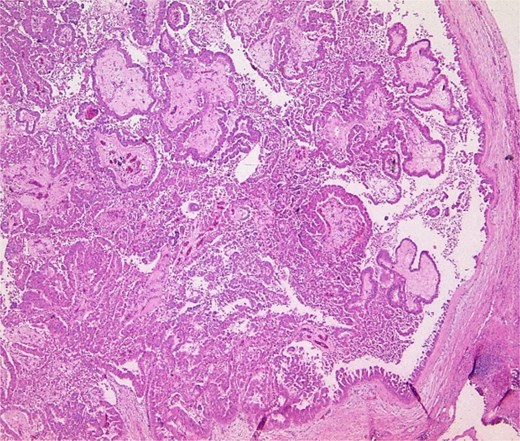

A left hemihepatectomy was performed successfully. Intraoperative findings revealed a tumor confined to segments II and III of the liver. The resected specimen measured 12 cm in diameter. Histopathological analysis confirmed the diagnosis of intrahepatic cholangiocarcinoma associated with Caroli's disease (Fig. 4). The resection margins were free of tumor involvement.

Pathology specimen shows markedly cystic dilated intrahepatic bile ducts with infiltrating adenocarcinoma.